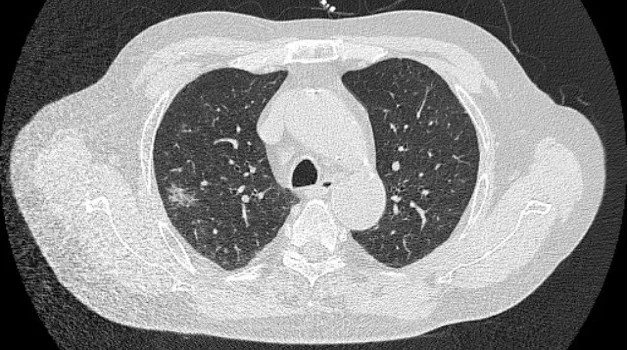

第一阶段(2024年5月):因“恶心呕吐”于当地诊断为慢性萎缩性胃炎、胃窦溃疡,对症治疗后症状反复,继而出现咳嗽、咳白痰,胸部CT提示右肺炎症,抗感染治疗无效。

2024年6月10日肺部CT平扫影像